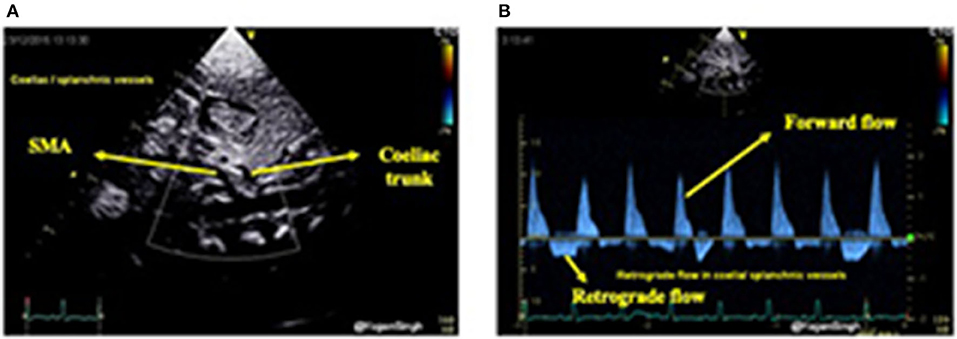

Similarly, celiac trunk or superior mesenteric artery can be interrogated using pulsed wave Doppler in the sagittal abdominal view (Figure 10). Doppler assessment of the anterior cerebral artery in the mid-sagittal view of brain ultrasound can be performed and retrograde flow during diastole would suggest significant ductal shunt—similar to coeliac or superior mesentery artery Doppler assessment. However, to date the clinical relevance and long term outcomes of the deranged cerebral Doppler flow patterns remain unknown (33).

Figure 10. Color flow mapping and Doppler assessment of blood flow in the coeliac trunk and superior mesenteric artery in sub-costal sagittal view. (A) Showing color flow mapping of the coeliac and superior mesenteric arteries; and (B) showing retrograde blood flow during diastole in the the coeliac and superior mesenteric arteries indicating “ductal steal” in presence of a large PDA.